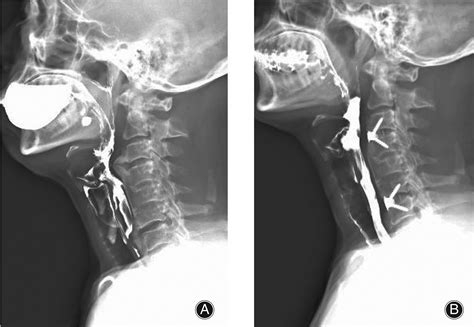

A Video Swallow Study, also known as a modified barium swallow study, is a diagnostic procedure that uses fluoroscopy to observe the swallowing process in real-time. During the study, the patient ingests barium-coated food or liquid, which makes the swallowing structures visible on X-ray images. This allows healthcare professionals to identify any abnormalities or obstructions in the swallowing pathway.

1. Patient Positioning: The patient is positioned in front of a fluoroscopy machine, which captures real-time X-ray images.

2. Barium Administration: The patient is given barium-coated food or liquid to swallow. The barium makes the swallowing structures visible on the X-ray.

3. Swallowing Observation: The healthcare provider observes the swallowing process on a monitor, noting any abnormalities or obstructions.

4. Data Collection: The fluoroscopy images are recorded for detailed analysis and documentation.

Interpreting the results of a Video Swallow Study involves analyzing the fluoroscopy images to identify any abnormalities in the swallowing process. Key areas of focus include:

• Oral Phase: The movement of the tongue and the coordination of the oral muscles.

• Pharyngeal Phase: The movement of the bolus (food or liquid) through the pharynx and the coordination of the pharyngeal muscles.

• Esophageal Phase: The movement of the bolus through the esophagus and into the stomach.